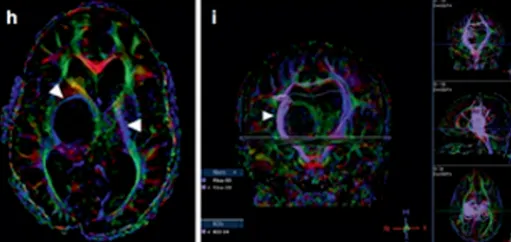

症状不严重,手术风险太大,做完可能比现在更差,医生评估不具有手术指征。然而,肿瘤一直长大,而且长出了很多小的囊肿。同侧内囊(负责人体肢体运动)也向前外侧移位,导致马修从左上肢震颤到急性偏瘫。

4个月后,马修的偏瘫没有改善,鲁特卡教授又为其行经胼胝体半球间入路及肿瘤切除术,顺利切除了肿瘤。术后,马修的偏瘫改善,生长和智力发育都正常。